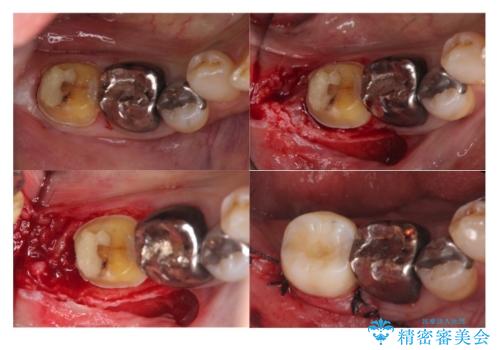

⑴虫歯除去し、仮歯とする

⑵歯周外科手術

歯ぐきの中まで虫歯の場合は、まず、虫歯も取りきることが難しいです。

また、被せ物のきわを歯ぐき深くに設定してしまうことになり、正確な歯型がそのままでは取れません。また、歯ぐきのみを取り除いても一時的な処置となり、また歯ぐきが再生してしまうため、最終的には歯ぐきの腫れが治りません。